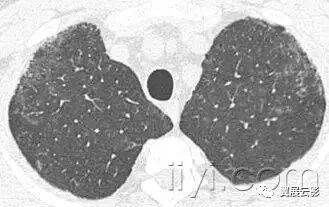

三十九、马赛克征

CT:本征象表现为不同的密度成片状镶嵌,可为间质性病变、闭塞性小气道病变(图)或者血管阻塞性疾病。马赛克征比马赛克样少血或者低灌注具有更强的诊断含义。由于支气管或细支气管阻塞导致的空气滞留可以导致局部的密度减低,在呼气相CT上表现更加明显。

该征象也可以见于间质性肺部疾病,特征是磨玻璃影,此时高密度代表间质性病变,低密度代表正常的肺。